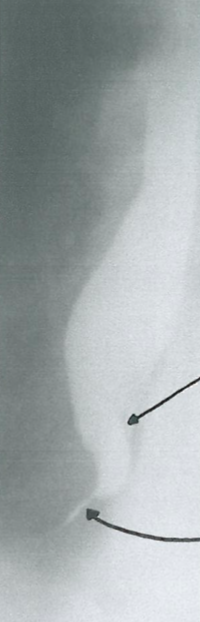

Stenoză esofagiană benignă (postcaustică)